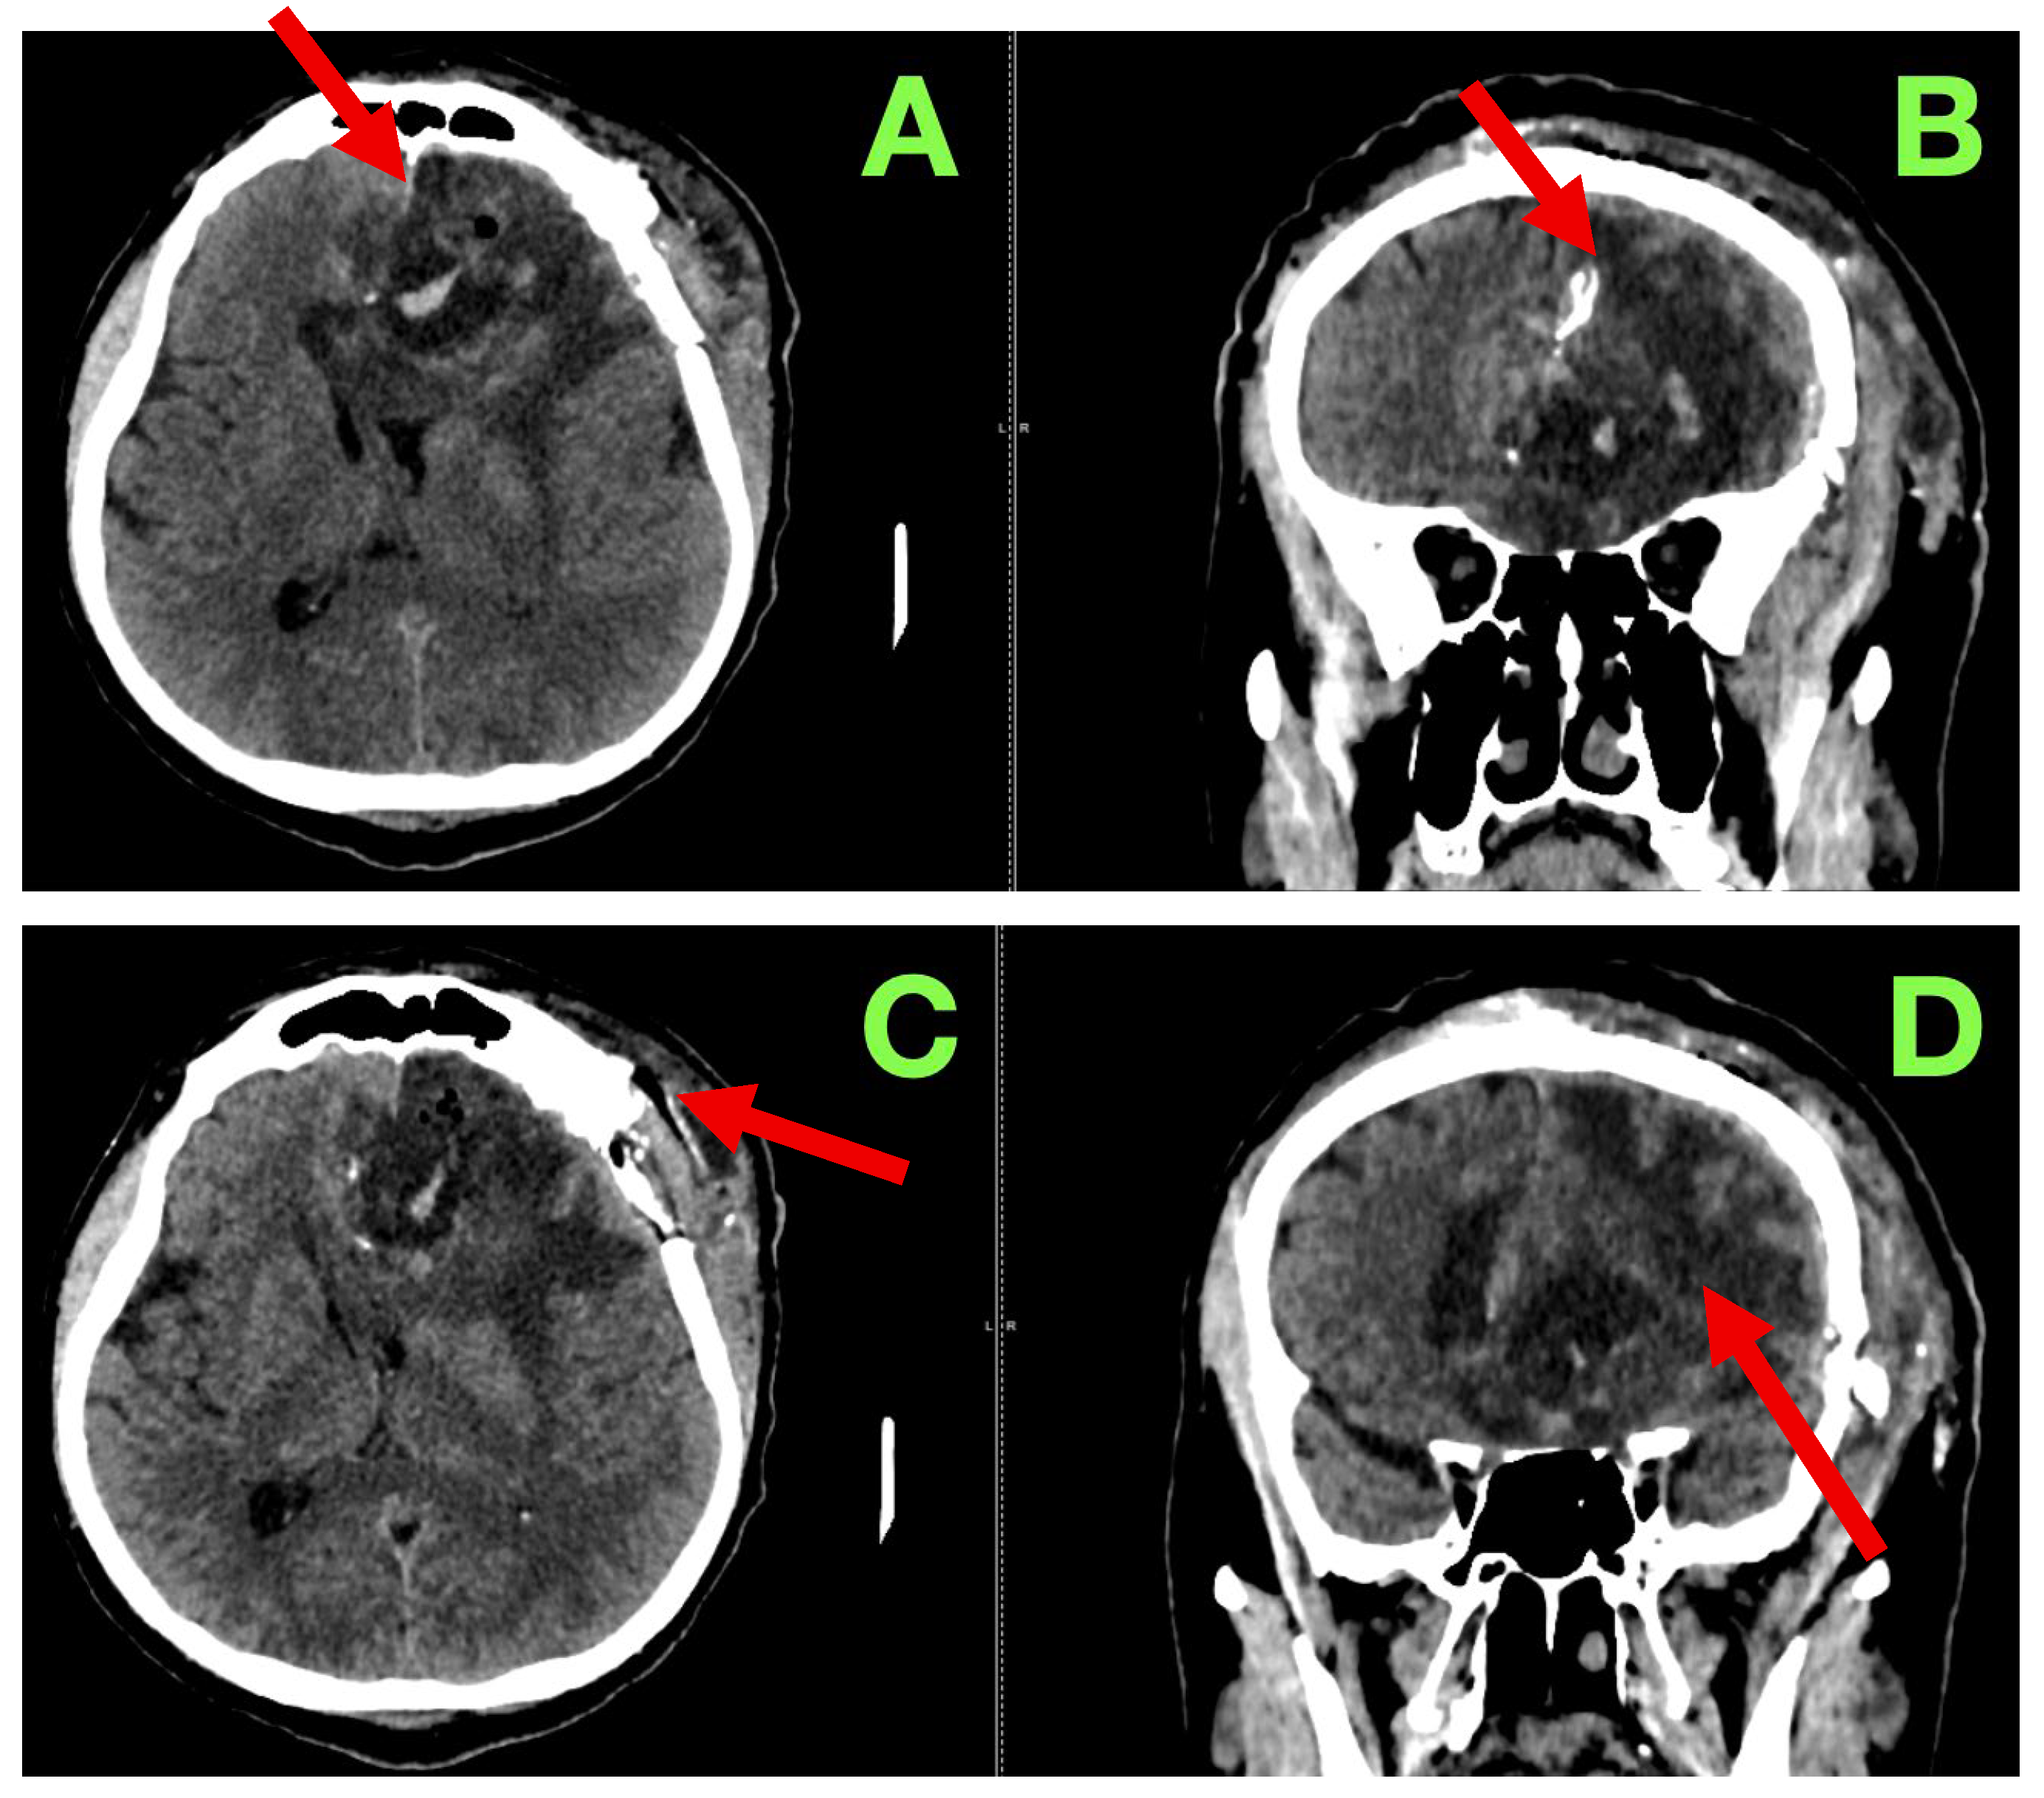

A non-contrast cranial CT scan was obtained within 4 h of the procedure to evaluate the resection cavity and rule out acute complications (Figure 2).

Figure 2. Immediate post-operative non-contrast CT scan. (A): Axial section showing a well-defined hypodense surgical cavity in the left frontobasal region (red arrow), corresponding to the zone of resection. No acute hemorrhage is present. A thin hyperdense rim along the cavity walls likely represents blood residue and oxidized cellulose (hemostatic material). (B): Coronal reconstruction demonstrating the vertical extent of the resection cavity (red arrow), which reaches the superior frontal gyrus and approaches—but does not breach—the genu of the corpus callosum. The midline remains centered, with no evidence of subfalcine or transtentorial herniation. (C): Lower axial slice illustrating the anterior margin of the resection cavity (red arrow). The basal ganglia and anterior limb of the internal capsule are preserved, and no new infarct or hematoma is detected. (D): Coronal view confirming decompression of the previously compressed left frontal horn (red arrow). No hydrocephalus or extra-axial collections are present. A subtle air–fluid level is visible within the cavity, consistent with expected early post-operative change.